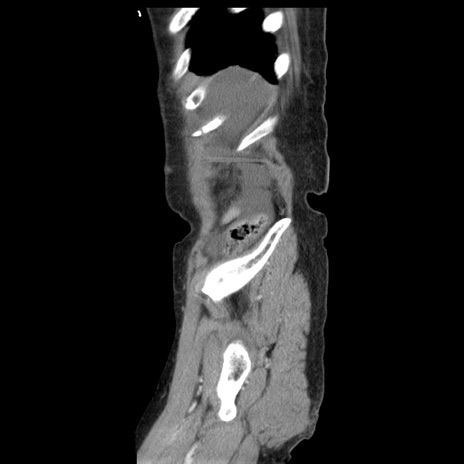

横断像

【症例】80歳代女性

【主訴】腹痛

【現病歴】8時間前から腹痛あり来院。

【既往歴】糖尿病、脂質異常症、子宮体癌にて子宮全摘術

【身体所見】意識清明・会話良好だが腹痛で苦悶様、全腹部にわたって反跳痛と圧痛あり

【データ】WBC 13600、CRP 0.14、LDH 224、CK 90